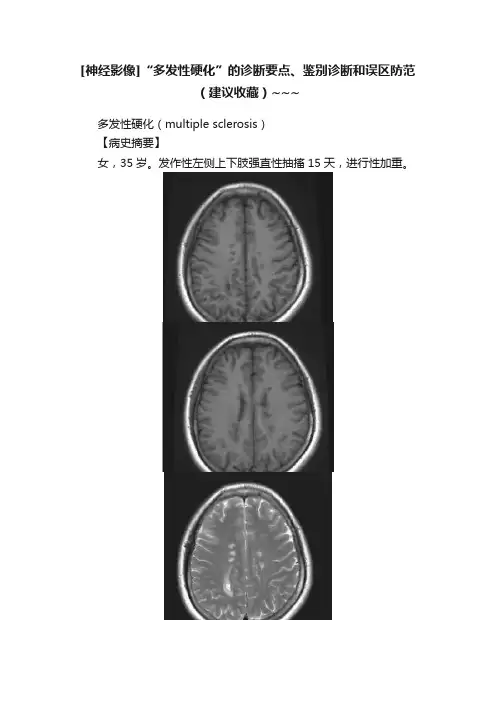

[神经影像]“多发性硬化”的诊断要点、鉴别诊断和误区防范(建议收藏)~~~多发性硬化(multiple sclerosis)【病史摘要】女,35岁。

发作性左侧上下肢强直性抽搐15天,进行性加重。

图1多发性硬化MRI检查【影像所见】图1A、B、C、D、E、F,横轴面T1WI、T2WI及矢状面T2 Flair 可见侧脑室旁脑白质内多发斑点及片状长T1长T2信号,边界模糊,部分病灶垂直于侧脑室体部分布。